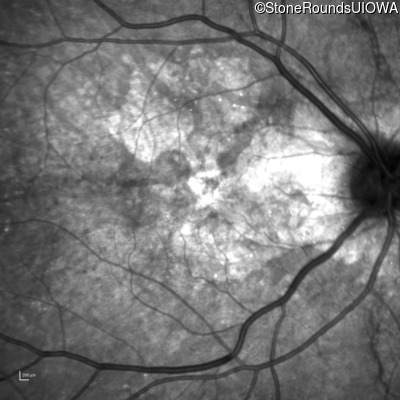

Infrared Fundus Photograph - Left - 20/25 +3

Exemplar